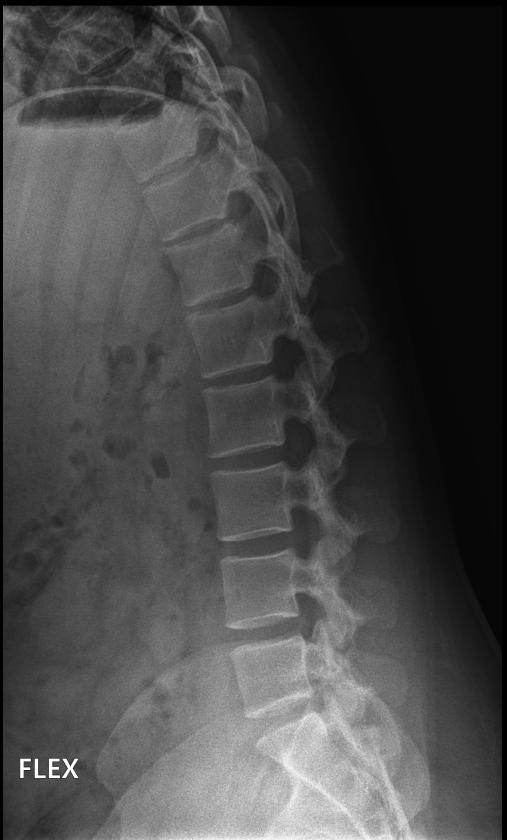

척추분리증인가요??(엑스레이 있어요)

한 병원에서는 척추분리증이라고 하고 한 병원에서는 척추분리증이 아니라고 해서요. 혹시 아래 사진에서 척추분리증 소견이 보이는 사진이 있나요??

여기까지가 a병원에서 찍은 사진이고 아래가 b병원에서 찍은 사진이에요!

• 1번 째 사진

• 2번 째 사진

척추분리증 맞습니다.

A병원 세번째 사진의 아래 부위에 척추분리증이 있는게 맞습니다.

B병원 사진에서는 비교적 흐리게 보이지만 잘 보면 B병원 엑스레이에서도 같은 부위에 분리증을 확인할 수 있습니다.